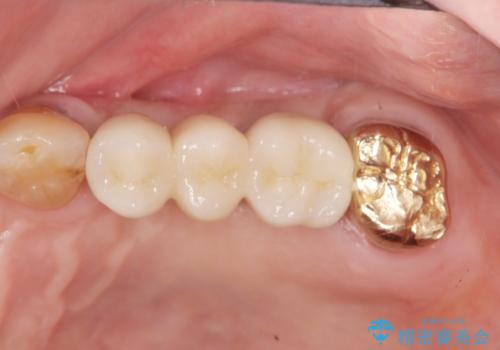

- 106.7万円(インプラント×2・チタンカスタムアバットメント×2・ジルコニアクラウン×3・仮歯×3)費用は治療当時の料金となります

入れ歯とは比べものにならないくらいしっかりと噛めるようになり、大変喜んでいただくことができました。